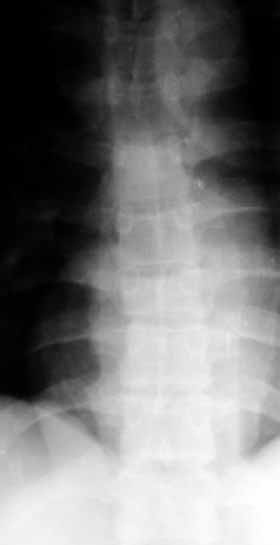

A male 39 years old some times rolled within a car June 12. Clinically no neurological deficit. Does the case require operative reduction/stablization? If no how would you manage the case?

A CT would be helpful to determine if there is middle column involvement. Also it would help determine if the posterior interspinous ligament is intact (lack of interspinous widening. The available images appear to show an anterior column only injury. If other imaging tests confirm this combined with normal neurological function nonoperative treatment with a hyperextension brace or nothing is appropriate.

Agreed, except that loss of posterior vertebral body height on the lateral radiograph suggests middle column involvement as well, and therefore a diagnosis of burst fracture. This is confirmed on the AP by (albeit subtle) widening of the pedicles at the level of injury. In keeping with this diagnosis, the lateral also suggests retropulsion of fracture fragments into the canal. I concur that unless there is associated facet subluxation or interspinous widening on CT (possible, but unlikely given the well-maintained alignment and given that on the AP radiograph the spinous processes seem reasonably equidistant) this is a stable burst fracture that I would treat with a TLSO for 3 months.

This presumablly is a stable compression of the body of T8 or thereabout, without neurology. Keep him in bed until the acute pain subsides and then start him on physiotherapy.